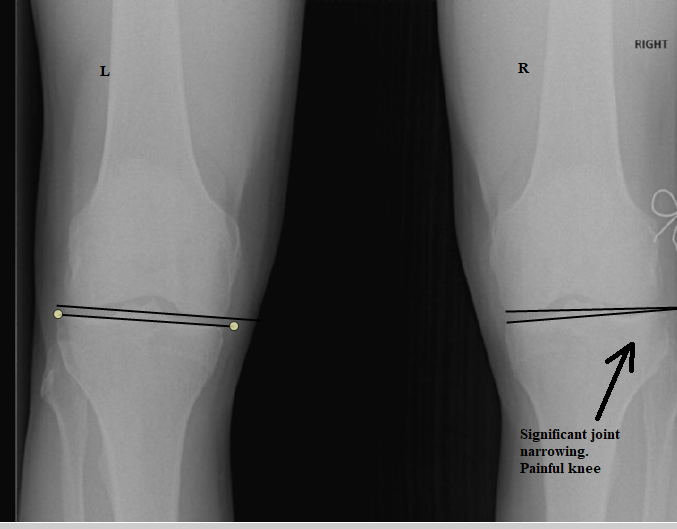

After his initial assessment we referred Jim for a weight bearing x-ray of both his feet and knees to measure the level of misalignment. We found significant joint misalignment's (subluxations) in both feet, having a direct impact on the right knee. The subluxation you can see on the x-ray below highlights narrowing of the joint space.

Can you imagine the pain experienced when 3 times your body weight is forced through the joints when running!